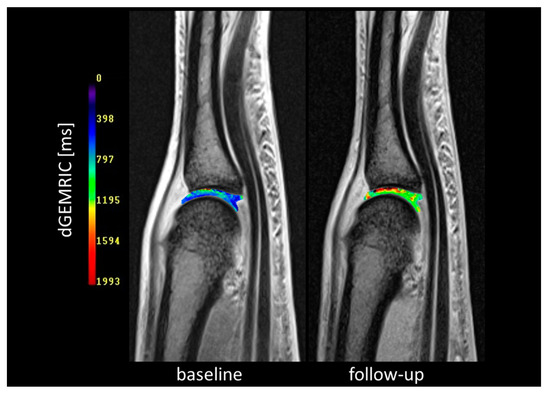

3.3. Cartilage Integrity (dGEMRIC)

- Tiderius, C.J.; Sandin, J.; Svensson, J.; Dahlberg, L.E.; Jacobsson, L. Knee cartilage quality assessed with dGEMRIC in rheumatoid arthritis patients before and after treatment with a TNF inhibitor. Acta Radiol. 2010, 51, 1034–1037. [Google Scholar] [CrossRef]